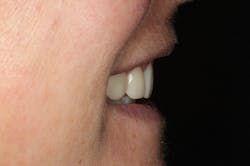

In this situation, we were able to achieve all of our functional and esthetics goals, which resulted in a happy patient (figures 22 and 23). The soft-tissue architecture was revised. The incisal edge positions and proportions were corrected. The shade, as well as the micro- and macro-esthetics, was improved. The exposed dentin and pulps of teeth Nos. 7–10 were covered and protected. Most importantly, we fulfilled the 5 requirements of occlusal stability for long-term functional success (figures 24 and 25).